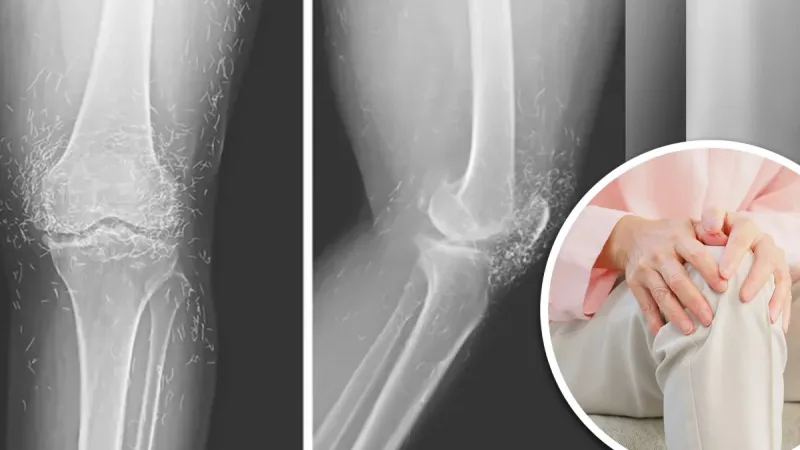

شاركت امرأة تبلغ من العمر 65 عاماً تجربتها مع العلاج، بعد أن عانت هشاشة العظام في الركبة «وهي حالة تنكسية تصيب المفاصل وتُسبب الألم والتيبس»، وأوضحت أنها بدأت بالعلاجات التقليدية مثل المسكنات، ومضادات الالتهاب، وحقن الستيرويد، لكن هذه الأدوية أدت لاحقاً إلى مشاكل صحية في المعدة دون أن تخفف من آلام الركبة.

وبعد فشل العلاجات الطبية، لجأت إلى طريقة «الوخز بخيوط الذهب»، حيث خضعت لعدة جلسات زُرعت خلالها مئات من الخيوط الذهبية في ركبتيها. إلا أن نتائج الفحوص الأخيرة أظهرت تلفاً في الأنسجة المحيطة، وظهرت أعراض التهاب مزمن في المنطقة.